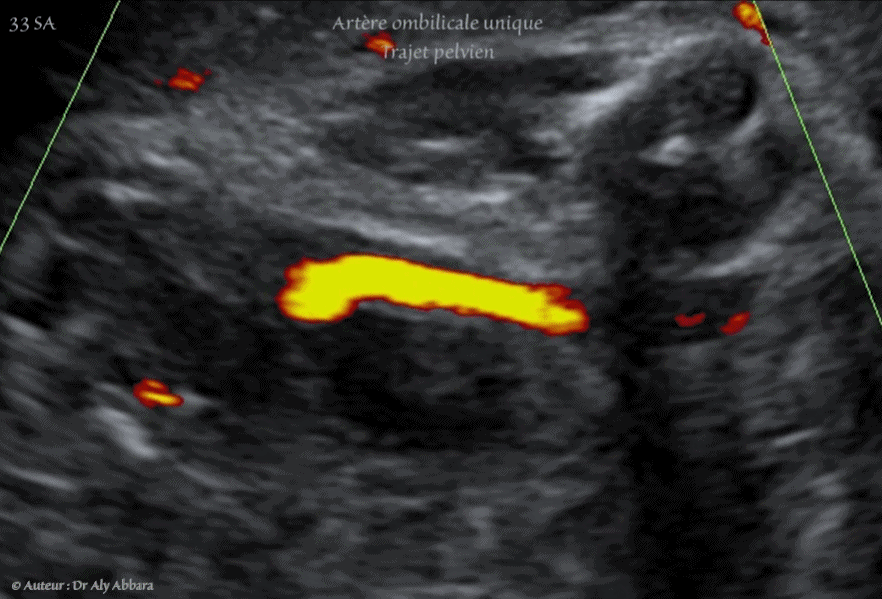

- Image échographique animée montrant, grâce au Doppler couleur de type Dynamic-Flow, la présence d'une artère ombilicale unique (AOU) dans sa portion pelvienne, coiffant la vessie après sa naissance de l'artère iliaque interne, puis atteignant en avant de la vessie l'ombilic, puis le cordon ombilical.

Le diagnostic échographique est possible par la réalisation d'une coupe transversale sur le cordon ; l'utilisation du Doppler couleur facilite ce diagnostic. Pour déterminer le côté de l'artère absente, il faut réaliser une coupe transversale au niveau de la vessie, sur cette coupe, le Doppler couleur met en évidence l'artère ombilicale manquante.